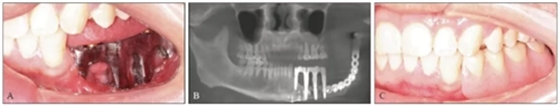

卸下患者口內(nèi)的35~37臨時(shí)個(gè)性化復(fù)合基臺(tái)保護(hù)帽和34復(fù)合基臺(tái)保護(hù)帽,注射生理鹽水沖洗種植體及周?chē)浗M織,口內(nèi)試戴純鈦鑄造桿(圖15A),拍攝CBCT示鑄造桿與種植體復(fù)合基臺(tái)對(duì)接良好(圖15B)。將34~37膠托活動(dòng)義齒就位于鑄造桿上部Locator附著體,囑患者做正中咬合及側(cè)方咬合,調(diào)磨咬合高點(diǎn),拋光,完成最終修復(fù)體的戴入(圖15C、D)。囑修復(fù)后修復(fù)體及牙周維護(hù)。